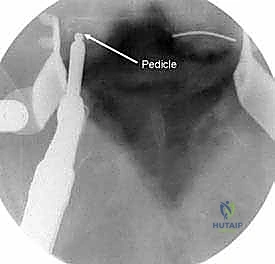

السويقات الفقارية (Pedicles): دعامة التثبيت الأساسية والمحورية

تعتبر السويقة الفقارية (Pedicle) جسرًا عظميًا أسطوانيًا يربط الأجزاء الخلفية للفقرة (القوس الفقري) بالجسم الفقري الأمامي الضخم. في جراحة دمج الفقرات الحديثة، تعتبر السويقة نقطة التثبيت الرئيسية والأقوى للمسامير المستخدمة في العملية (Pedicle Screws). يختلف شكل وحجم وزاوية السويقات بشكل كبير على طول العمود الفقري، وفهم هذه الفروق الدقيقة أمر بالغ الأهمية للجراح لضمان وضع المسامير بأمان تام وفعالية قصوى دون الإضرار بالأعصاب أو الأوعية الدموية.

عملية دمج الفقرات (Spinal Fusion) هي إجراء جراحي يهدف إلى ربط فقرتين أو أكثر بشكل دائم، مما يزيل الحركة غير الطبيعية والمؤلمة بينهما، ويعيد الاستقرار الميكانيكي إلى العمود الفقري. في حالتنا هذه، يتم التركيز بشكل خاص على المنطقة الصدرية القطنية (Thoracolumbar Junction)، وهي المنطقة الانتقالية الحرجة التي تربط الجزء العلوي من الظهر (القفص الصدري الصلب) بالجزء السفلي (المنطقة القطنية المتحركة). يتم التثبيت باستخدام أدوات طبية معدنية متطورة (Instrumentation) مثل المسامير السويقية (Pedicle Screws) والقضبان المصنوعة من التيتانيوم.